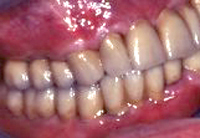

Abb. 13 - Ein Blick ins Seitengebiss vor der Sanierung.

Abb. 14 - Ein Blick ins Seitengebiss nach der Sanierung.